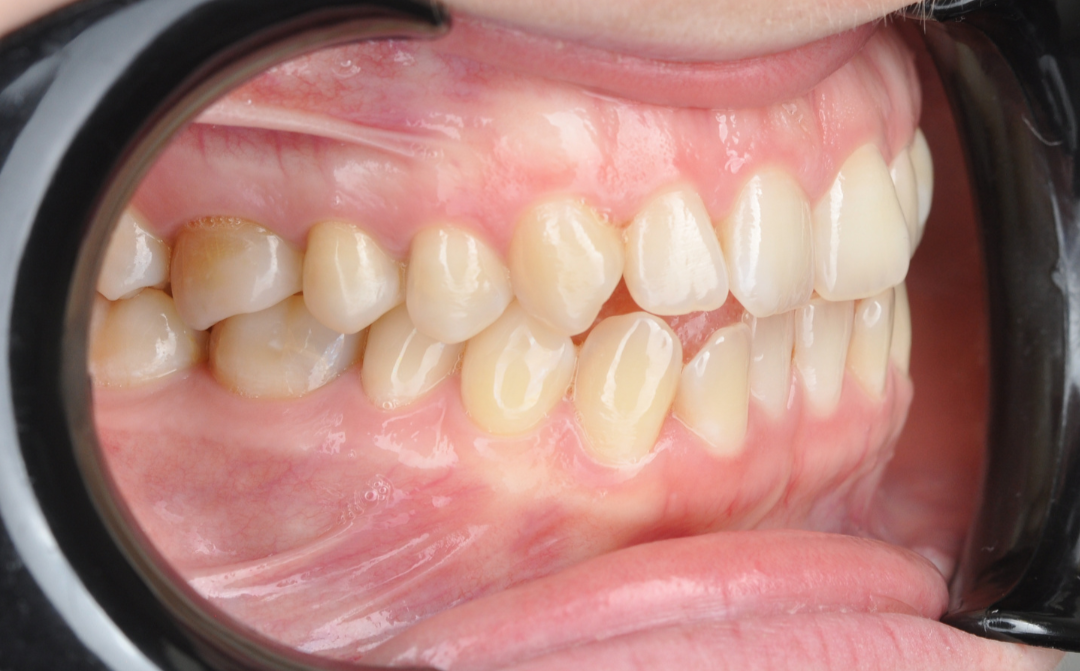

Этап №3

Ортодонтическая коррекция.

Стоматолог-ортодонт зафиксировал комбинированную брекет-систему (сверху керамические, а снизу – металлические брекеты).

Ключевые задачи ортодонта:

- Исправление прямого прикуса (одной из частых причин дисфункции ВНЧС).

- Изменение положения зубов.

- Доведение контактов челюстей до физиологически правильного смыкания.